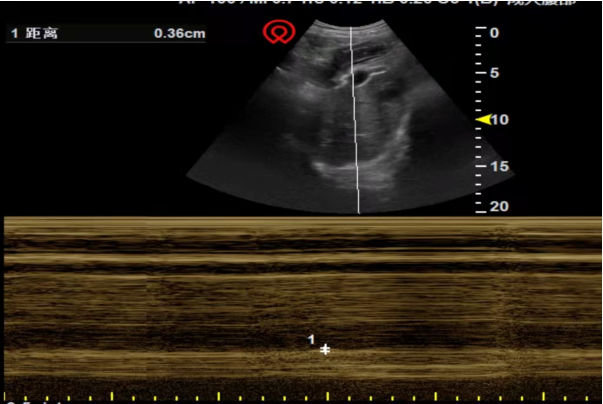

气管插管后充分引流分泌物,呼吸机参数下降,每日SBT脱机拔管评估,患者行SBT 1 h内均出现气促、心率快、血压高、大汗淋漓表现。行床旁膈肌超声检查,显示平静呼吸期间移动度<10~15 mm,提示双侧膈肌活动度弱。

若床旁膈肌超声显示膈肌厚度<2 mm或膈肌增厚率<20%,可以诊断为双侧隔肌麻痹。结合本例患者膈肌超声结果,可以判断为双侧膈肌麻痹。

评估:上肢肌力3级,下肢肌力2+级;膈肌厚度0.16 mm,动度0.36 cm;下肢B超提示无深静脉血栓;氧饱和度97%(PSV模式,FiO2 40%)。